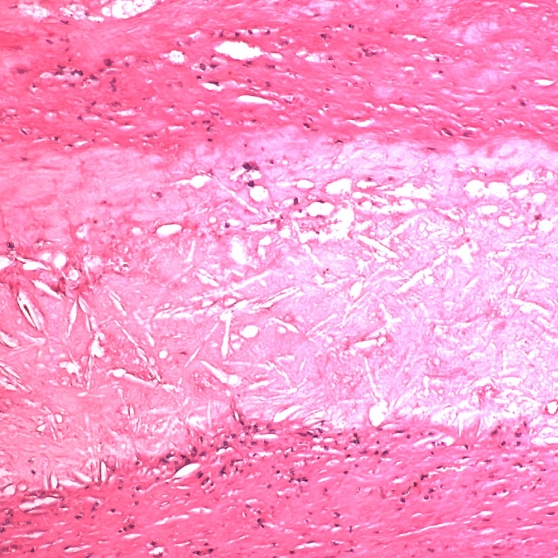

Pulmonary arterial hypertension is a progressive condition characterized by high blood pressure in the pulmonary arteries, which carries blood from the heart to the lungs. Common symptoms include dizziness, shortness of breath, general fatigue and even periodic fainting. PAH occurs in about 15 out of every million adults.